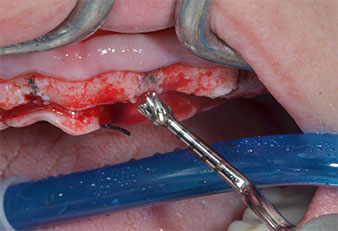

Ein flammenförmiges, diamantiertes piezochirurgisches Instrument (Piezomed I1) wurde verwendet, um die Implantatpositionen zu markieren und die Pilotpräparationen durchzuführen (Abb. 3). Dabei wurde darauf geachtet, eine Auf- und Abbewegung mit reduzierter Leistung, voller Spülung und niedrigem Druck (unter 300 g) anzuwenden. Als Nächstes wurde ein Pilotinstrument (Piezomed I2A/I2P) zur initialen Erweiterung der Implantatlager auf einen Durchmesser von 2 mm verwendet (Abb. 4), gefolgt von einem 3-mm-Instrument (Abb. 5).

Wegen des relativ harten Knochens (D2) an den Positionen 11 und 21 wurden die 10 mm langen Implantatlager in diesem Bereich abschließend mit einem 4-mm-Spiralbohrer, dem chirurgischen Winkelstück WS-75 L von W&H und dem W&H Implantmed Implantologiemotor in Verbindung mit dem optionalen W&H Osstell ISQ module präpariert. Im Gegensatz dazu wurde der weiche Knochen der Implantatlager im Seitenzahnbereich mit dem Piezomed I3P auf den abschließenden Durchmesser von 3 mm erweitert. Die Implantate wurden dann transgingival eingesetzt, die Einheildauer betrug drei Monate (Abb. 6-10). Die vorhandene Prothese wurde auf vier provisorischen Implantaten abgestützt (Abb. 8).